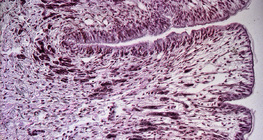

100x magnification